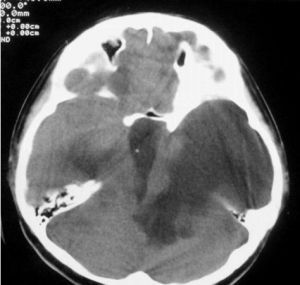

4.頭顱CT或MRI可以顯示雙側腦室對稱性擴大,第三腦室及第四腦室也擴大,腦萎縮。連續顱內壓監護可發現患者熟睡後的眼動期出現顱內壓升高現象,據此可與腦萎縮引起的老年性痴呆相鑑別。腰椎穿刺示腦脊液壓力正常,CSF檢查正常。

1.頭顱CT或MRI可以顯示雙側腦室、第三腦室及第四腦室擴大,腦萎縮。

應與老年性痴呆及腦萎縮相鑑別。這些疾病臨床上無顱內壓增高,但有原發病的症狀與特徵。CT、MRI顯示腦室系統和蛛網膜下隙相對增大,但腦室形態正常,第四腦室多不受累。局限性腦萎縮可見局部腦溝、腦池增寬,其餘蛛網膜下隙正常,而腦積水患者的腦室擴大程度與蛛網膜下隙多不成比例,腦室形態異常,腦室周圍水腫。